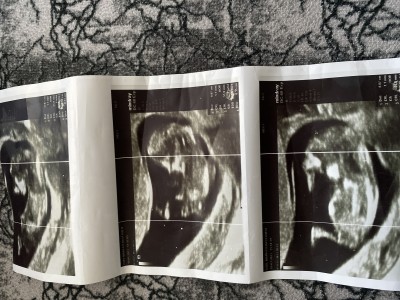

Önceliğim her daim saglıklı olması tabiki ama insan merak ediyor bilgisi olan varsa sizlere zahmet tahminde bulunun. 1 kızım var ve oğlum ise 1yaşımda vefat ettibu yüzden dört gözle bekliyorum cinsiyeti

Erkek bacak arasında bir çıkıntı var  gibi